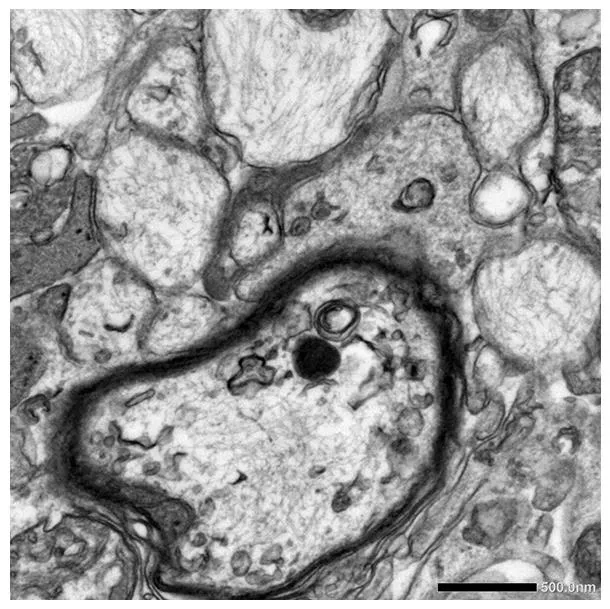

High Magnification

Loss of coating around nerve cells with degeneration

(demyelination/loss of myelin & axons)